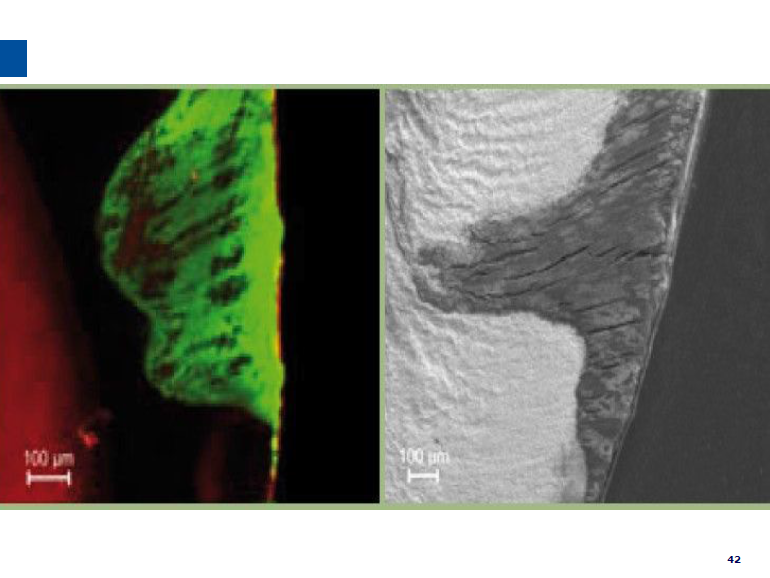

微创牙科治疗是一种全新的龋病治疗理念,着眼于疾病的早发现、早诊断、早治疗。树脂渗透治疗是介于再矿化治疗和充填治疗之间的一种创新的治疗手段,通过微量的去除牙体组织,达到加固脱矿釉质、阻止进一步脱矿的目的。

lcon渗透基于封闭釉质龋空隙的一种特殊树脂的渗透,封闭釉质龋小孔,从而阻断致龋酸传播途径,阻止龋病进一步发展。这种材料操作方法简单,对牙体组织损伤轻微,不用通过麻醉和磨切牙体来达到加固脱矿釉质,同时可以改变釉质龋表面的白色或棕色改变,达到美观修复效果,是对龋病微创治疗的突破。